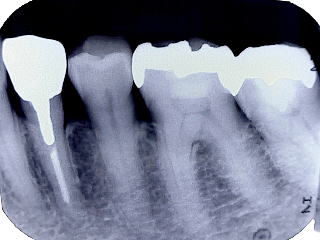

である。開業当初から当診療システムで38年間口腔管理をしている。Panorama、CTなどレントゲンを介しての顎骨・歯槽骨の形態・骨

量などを観察したもので、歯槽骨の吸収状態から診ても、ほぼ二十歳代に相当するように思われる。過去の論文を見ても、口腔内写真

(図15)2015年7月27日、83歳。高年齢と残存歯数ばかりが問題視されているが、歯槽骨の状態、歯肉、Pocketの状態を含めた歯周病を評価すべきである

歯周病治療38年経過:83歳(女性)残存歯数28本